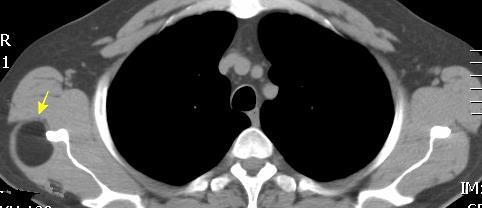

48 MASAS. LIPOMA SUBPECTORAL

Densidad similar al músculo con estriaciones internas de grasa

Hallazgo incidental . Región infraescapular 2% de TC del tórax. Bilateral 60%.

Burt AM et al. Imaging review of lipomatous musculoskeletal lesions. SICOT J2017/ Murphey MD et al. From the archives of the AFIP: benign musculoskeletal lipomatous lesions. Radiographics. 2004

Isointenso con grasa subcutánea